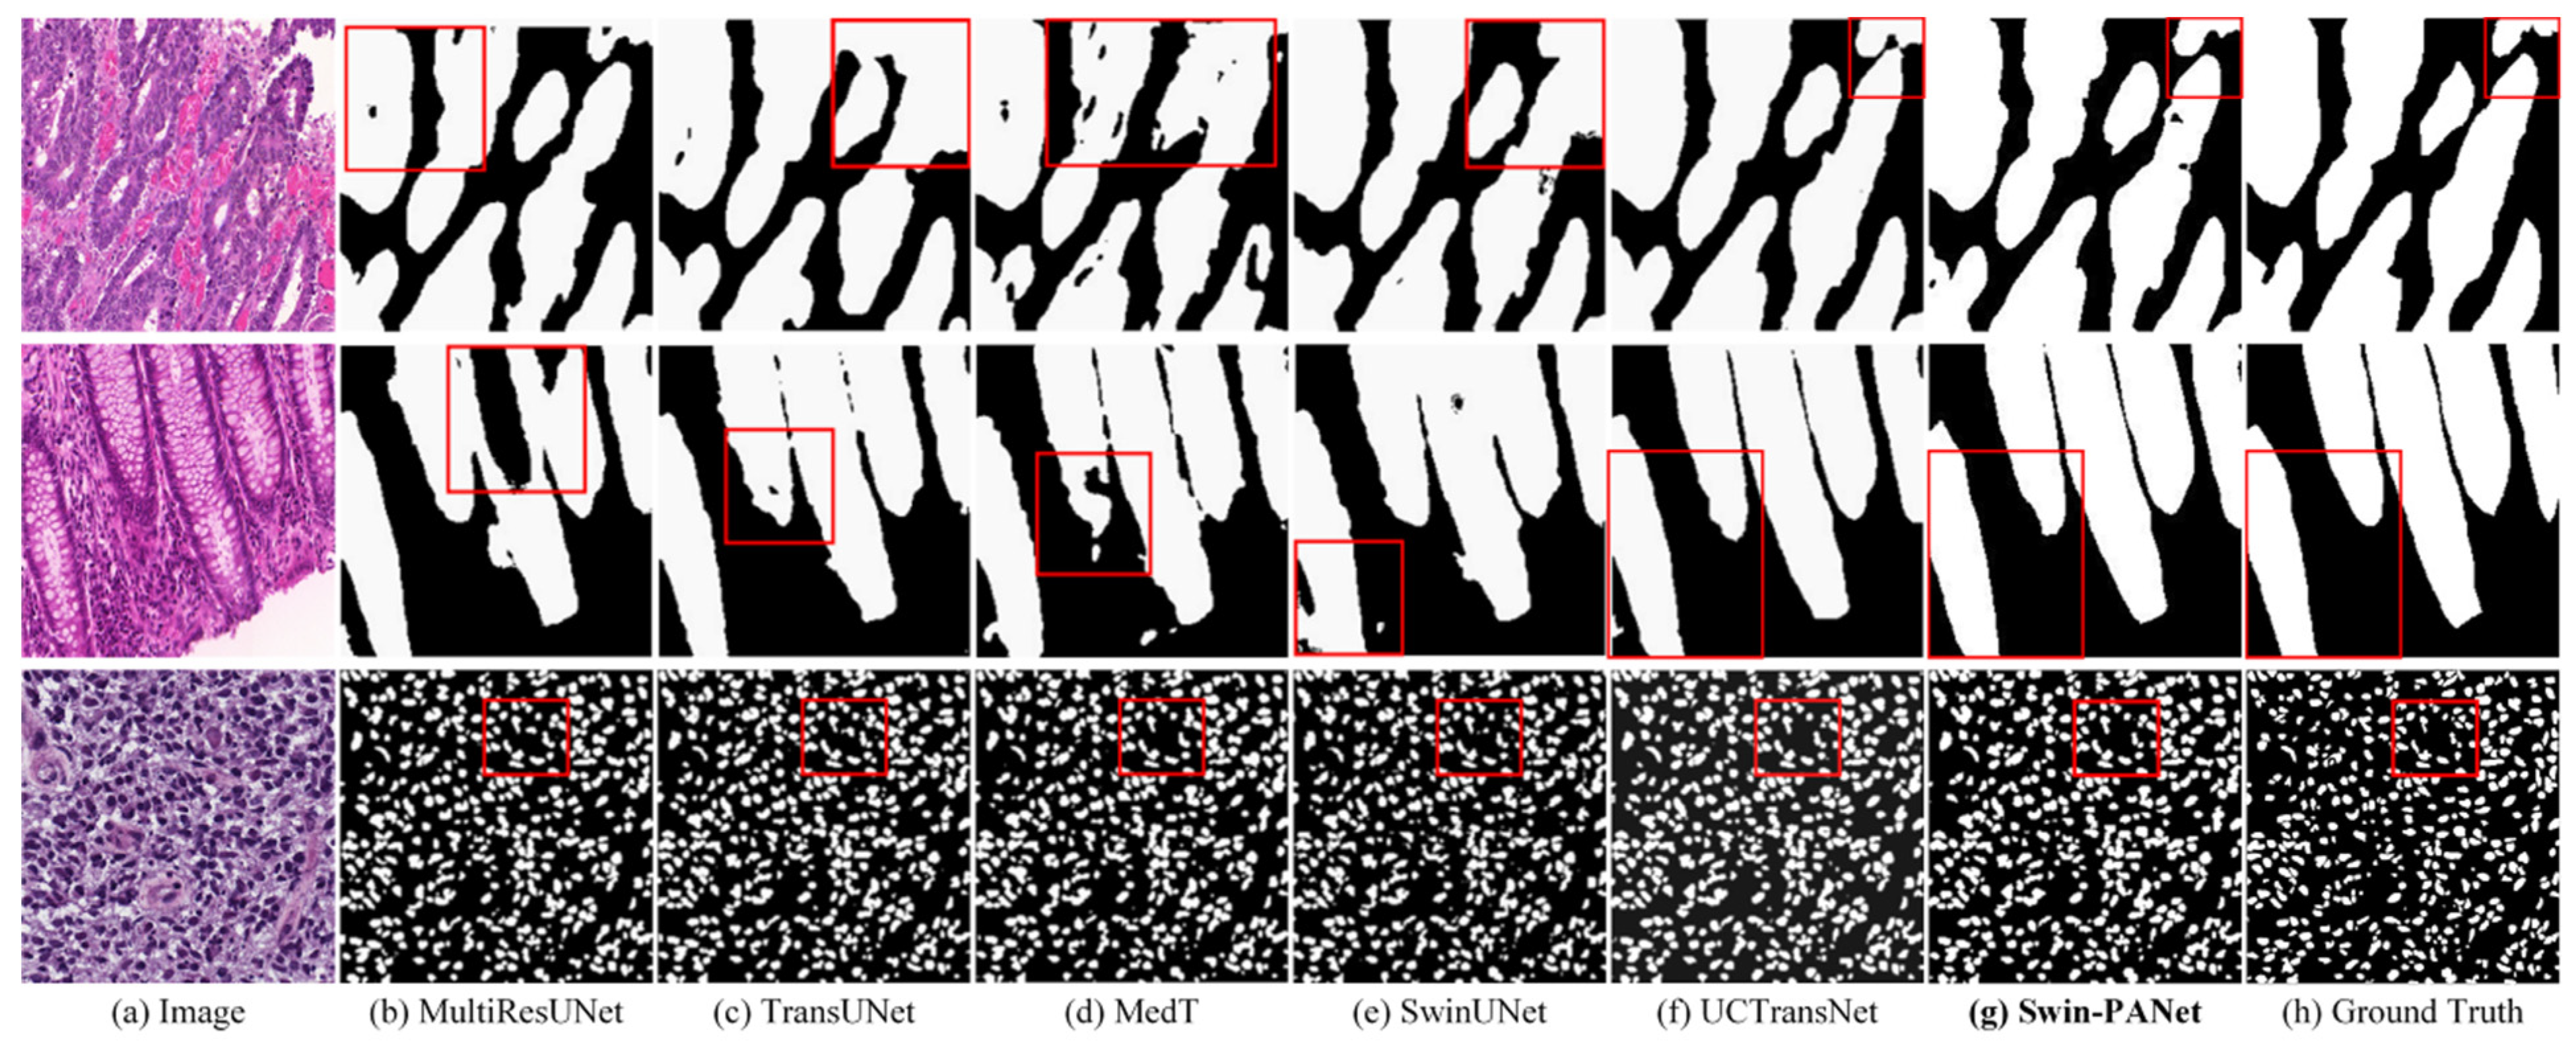

4.2. Comparisons with State-of-the-Art Methods on GlaS and MoNuSeg Datasets

| Network | GlaS | MoNuSeg | ||

|---|---|---|---|---|

| Dice (%) | IoU (%) | Dice (%) | IoU (%) | |

| U-Net (2015) | 86.34 | 76.81 | 73.97 | 59.42 |

| UNet++ (2018) | 87.07 | 78.10 | 75.28 | 60.89 |

| AttUNet (2018) | 86.98 | 77.53 | 76.20 | 62.64 |

| MRUNet (2020) | 87.72 | 79.39 | 77.54 | 63.80 |

| TransUNet (2021) | 87.63 | 79.10 | 79.20 | 65.68 |

| MedT (2021) | 86.68 | 77.50 | 79.24 | 65.73 |

| Swin-Unet (2021) | 88.25 | 79.86 | 78.49 | 64.72 |

| UCTransNet (2021) | 89.84 | 82.24 | 79.87 | 66.68 |

| UCTransNet-pre | 90.18 | 82.95 | 77.19 | 63.80 |

| Swin-PANet (ours) | 91.42 | 84.88 | 81.59 | 69.00 |